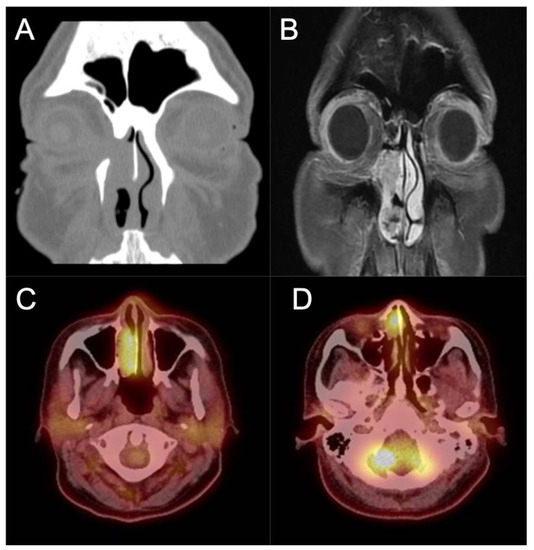

3. Imaging

- Jeon, T.Y.; Kim, H.J.; Chung, S.K.; Dhong, H.J.; Kim, H.Y.; Yim, Y.J.; Kim, S.T.; Jeon, P.; Kim, K.H. Sinonasal inverted papilloma: Value of convoluted cerebriform pattern on MR imaging. AJNR Am. J. Neuroradiol. 2008, 29, 1556–1560. [Google Scholar] [CrossRef] [PubMed]

- Yan, C.H.; Tong, C.C.L.; Penta, M.; Patel, V.S.; Palmer, J.N.; Adappa, N.D.; Nayak, J.V.; Hwang, P.H.; Patel, Z.M. Imaging predictors for malignant transformation of inverted papilloma. Laryngoscope 2019, 129, 777–782. [Google Scholar] [CrossRef]

- Zhang, L.; Fang, G.; Yu, W.; Yang, B.; Wang, C.; Zhang, L. Prediction of malignant sinonasal inverted papilloma transformation by preoperative computed tomography and magnetic resonance imaging. Rhinology 2020, 58, 248–256. [Google Scholar] [CrossRef]